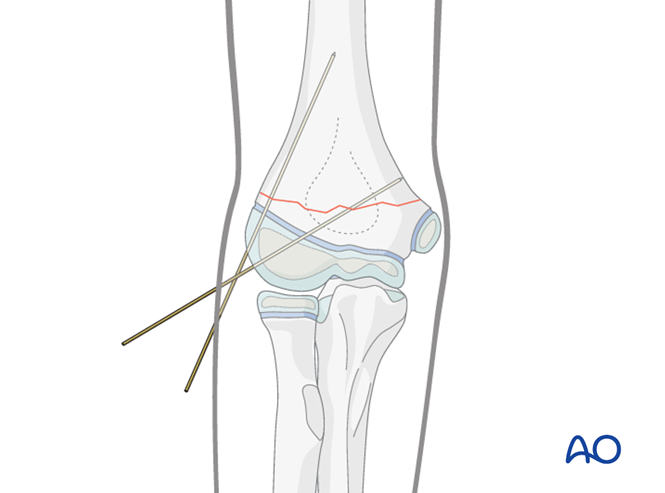

一,儿童骨化中心